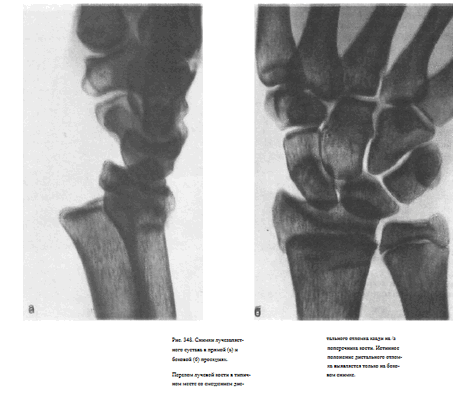

УКЛАДКИ ДЛЯ РЕНТГЕНОГРАФИИ ЛУЧЕЗАПЯСТНОГО СУСТАВА СНИМОК ЛУЧЕЗАПЯСТНОГО СУСТАВА В ПРЯМОЙ ЛАДОННОЙ ПРОЕКЦИИ

Назначение снимка. Этот снимок вместе со снимком в боковой проекции чаще всего используют при травмах.

Предплечье и кисть передней поверхностью прилежат к плоскости стола.

Кассета размером 18X24 см, наполовину перекрытая листом просвинцованной резины, располагается под снимаемой областью.

Проекция лучезапястного сустава, находящегося на уровне головки локтевой кости, соответствует срединной линии кассеты.

Пучок рентгеновского излучения направляют отвесно, в центр экспонируемой половины кассеты (рис. 342).

Информативность снимка. На снимке видны дисталыные метаэпифизы лучевой и локтевой костей, образующих между собой дистальный лучелоктевой сустав, и кости запястья. В образовании лучезапястного сустава принимают участие ладьевидная, полулуйная и трехгранная кости. Щель сустава неравномерной ширины: на уровне впадины лучевой кости она тонкая, на уровне локтевой кости значительно расширяется из-за отсутствия изображения хрящевого суставного диска, дополняющего суставную впадину, но не поглощающего рентгеновское излучение (рис. 343).

СНИМОК ЛУЧЕЗАПЯСТНОГО СУСТАВА В БОКОВОЙ УЛЬНАРНОЙ ПРОЕКЦИИ

Назначение снимка. Вместе со снимком в прямой проекции чаще всего используют для диагностики травмы.

Укладка больного для выполнения снимка. Больной сидит у стола.

Кисть располагают в плоскости, перпендикулярной плоскости стола.

Неэкспонированную ранее половину кассеты 18X24 см подкладывают под ульнарный край кисти и предплечья таким образом, чтобы ее средней линии соответствовала проекция суставной щели лучезапястного сустава.

Экспонированную половину кассеты перекрывают листом просвинцованной резины.

Пучок рентгеновского излучения направляют отвесно, соответственно проекции сустава (рис. 344).

Информативность снимка. На снимке видны дистальные концы локтевой и лучевой костей, проекционно накладывающиеся друг на друга; рентгеновская суставная щель лучезапястного сустава и кости запястья, среди которых отчетливее других выделяются полулунная, ладьевидная кость и кость-трапеция.

Частично видны также проекционно накладывающиеся одна на другую II—V пястные кости и отдельно— I пястная кость (рис. 345).